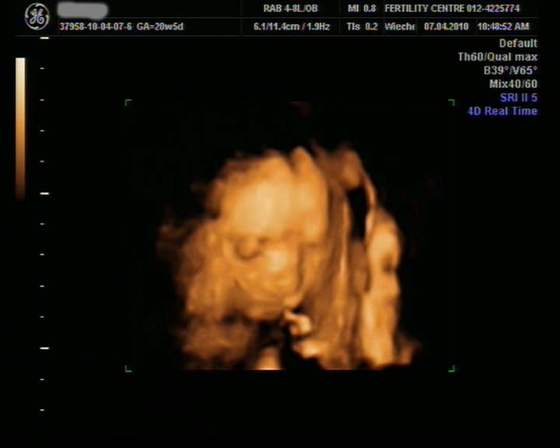

dziewczyny oto dowód na to że moja dzidzia to chłopczykśliczna stojąca fujarka:-)

No dokładnie,takie wypustki to na zdjeciach mój synek (w poprzedniej ciązy) miał na głowie ,raczkach i dłoniach,bo w tych miejscach był przytulony do powłok macicy i tak to zmieniało obraz.A tak jeszcze odnośnie tych zdjęć USG to niektore strasznie "zmieniają rzeczywistość" i tam gdzie nam się wydaje że jest główka to jest pupka ... to tak tylko dla przykładu